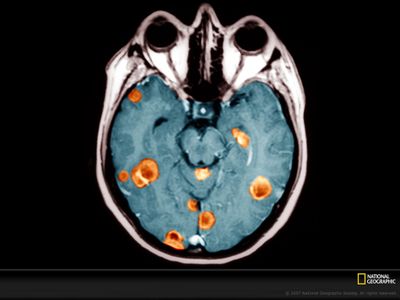

Molecular classification of cancer has entered clinical routine to inform diagnosis, prognosis, and treatment decisions. At the same time, new tumor entities have been identified that cannot be defined histologically. For central nervous system tumors, the current World Health Organization classification explicitly demands molecular testing, e.g., for 1p/19q-codeletion or IDH mutations, to make an integrated histomolecular diagnosis. However, a plethora of sophisticated technologies is currently needed to assess different genomic and epigenomic alterations and turnaround times are in the range of weeks, which makes standardized and widespread implementation difficult and hinders timely decision making. Here, we explored the potential of a pocket-size nanopore sequencing device for multimodal and rapid molecular diagnostics of cancer. Low-pass whole genome sequencing was used to simultaneously generate copy number (CN) and methylation profiles from native tumor DNA in the same sequencing run. Single nucleotide variants in IDH1, IDH2, TP53, H3F3A, and the TERT promoter region were identified using deep amplicon sequencing. Nanopore sequencing yielded ~0.1X genome coverage within 6 h and resulting CN and epigenetic profiles correlated well with matched microarray data. Diagnostically relevant alterations, such as 1p/19q codeletion, and focal amplifications could be recapitulated. Using ad hoc random forests, we could perform supervised pan-cancer classification to distinguish gliomas, medulloblastomas, and brain metastases of different primary sites. Single nucleotide variants in IDH1, IDH2, and H3F3A were identified using deep amplicon sequencing within minutes of sequencing. Detection of TP53 and TERT promoter mutations shows that sequencing of entire genes and GC-rich regions is feasible. Nanopore sequencing allows same-day detection of structural variants, point mutations, and methylation profiling using a single device with negligible capital cost. It outperforms hybridization-based and current sequencing technologies with respect to time to diagnosis and required laboratory equipment and expertise, aiming to make precision medicine possible for every cancer patient, even in resource-restricted settings.